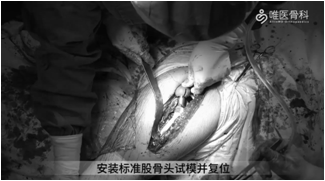

③假体大小确定后,仔细确认合适的股骨前倾角(参考髋臼杯的前倾角,使联合前倾角在安全范围内),然后安装标准股骨头试模并进行复位,检查髋关节稳定性和下肢长度。